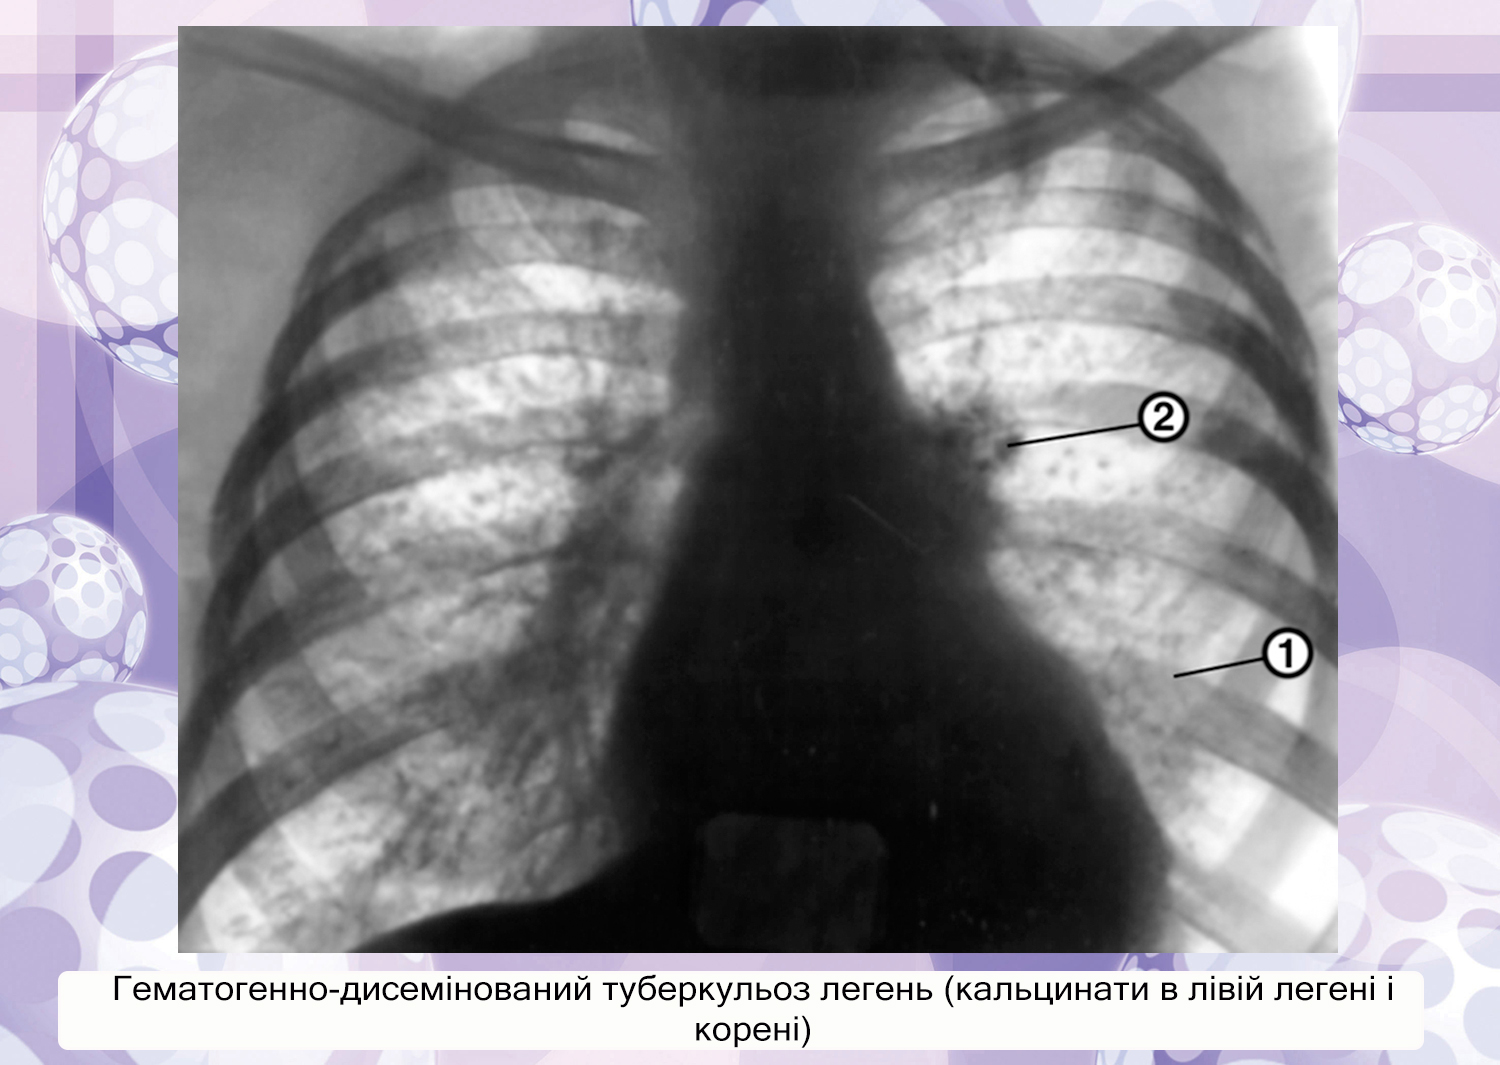

Диссеминированный туберкулез рентген

Подострый диссеминированный туберкулез рентген

Острый диссеминированный туберкулёз лёгких рентген

Диссеминированный туберкулёз лёгких рентген

Диссеминированный туберкулез

Милиарный диссеминированный туберкулез